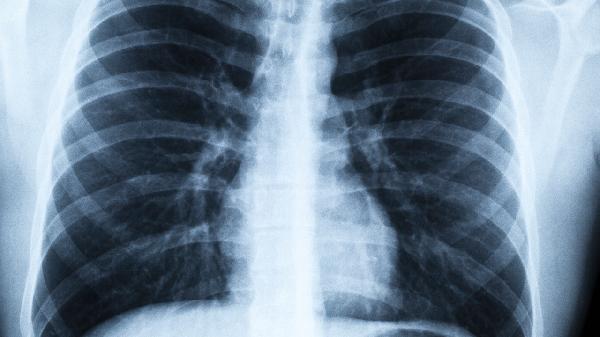

恢复期应保持每日8小时睡眠,避免剧烈运动。采用腹式呼吸训练改善肺功能,每日2次,每次10分钟。饮食以高蛋白、高维生素流质为主,少量多餐。定期复查胸部CT评估肺部炎症吸收情况,完全康复通常需要4-8周。